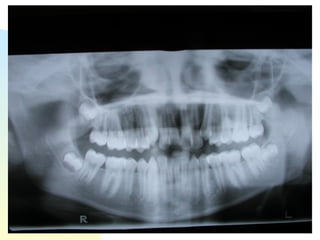

Patient   : J.R, male DOB :7/20/91, start of tx age: 12yr 9mo Ethnicity : American-born Hispanic, English-speaking Health Hx :  WNL, unremarkable Dental Hx :TMJ=WNL, OH=B+, midline=on, molar R&L= Cl 1, OB=40%, OJ= 1mm, dental anterior cross-bite, crowded max & mand anteriors, caries #15-O, #18-O,B, perio=WNL Psychosocial : Parents are separated,  1 younger sister,1 older sister.  Mom had ortho tx --- 4 premolars & 4-3rd molars extracted, “My braces hurt and I don’t want a lot of teeth pulled on my son”. Chief complaint :  “I don’t like the way my teeth stick out in front.”

31.6 35.7 44.4 42.3 29.6 Schwarz analysis SI=31.6, Max 4-4’s ideal = 39.6   actual 35.7 difference= -3.9 Max 6-6’s ideal= 47.6 actual 44.2 difference= -3.2  total -22.4 Man 4-4’s ideal= 39.6 actual 29.6 difference= -10 Man6-6’s ideal= 47.6 actual 42.3 difference= -5.3

31.6 35.7 44.442.3 29.6 Schwarz analysis SI=31.6, Max 4-4’s ideal = 39.6 actual 35.7 difference= -3.9 Max 6-6’s ideal= 47.6 actual 44.2 difference= -3.2 total -22.4 Man 4-4’s ideal= 39.6 actual 29.6 difference= -10 Man6-6’s ideal= 47.6 actual 42.3 difference= -5.3